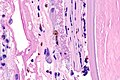

Microscopic

Features:

- See HSV.

IHC

- HSV1 +ve.